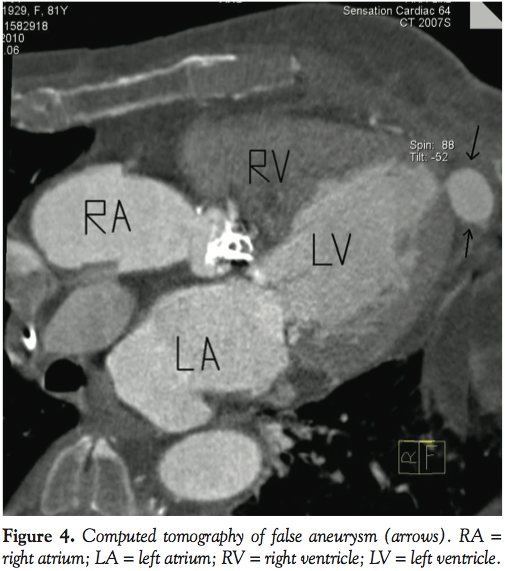

Computed tomography confirmed the echocardiographic findings with contrast enhancement of the false aneurysm in the early arterial phase (P4). Involvement of coronary arteries, especially the left anterior descending coronary artery, could not be found. A conservative observational management was performed, as the asymptomatic patient refused a surgical correction.